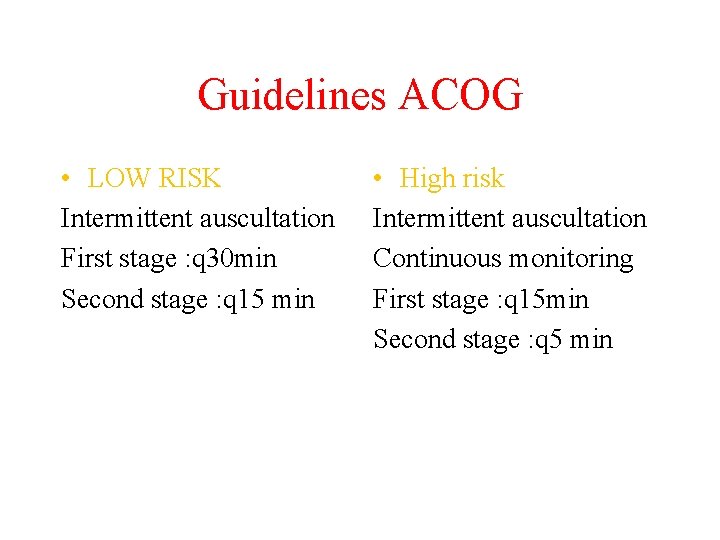

Guidelines ACOG • LOW RISK Intermittent auscultation First stage : q 30 min Second stage : q 15 min • High risk Intermittent auscultation Continuous monitoring First stage : q 15 min Second stage : q 5 min